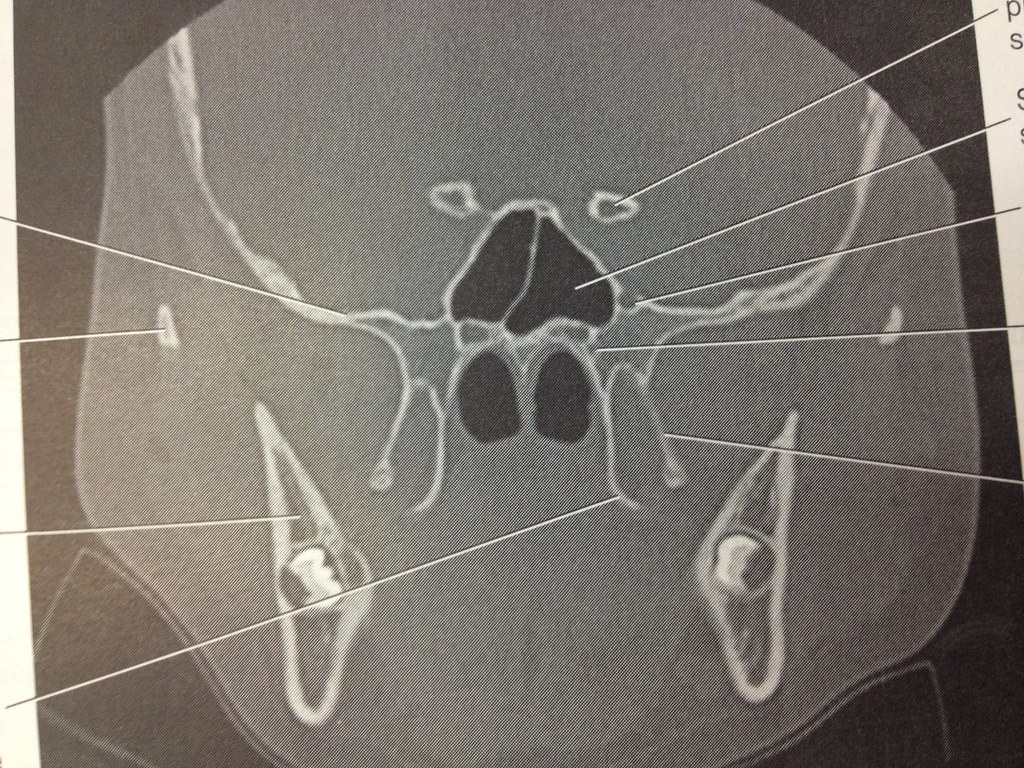

2.22 Coronal Sphenoid Bone | Sectional Anatomy, CT | Flickr

www.flickr.com

www.flickr.com

sphenoid coronal